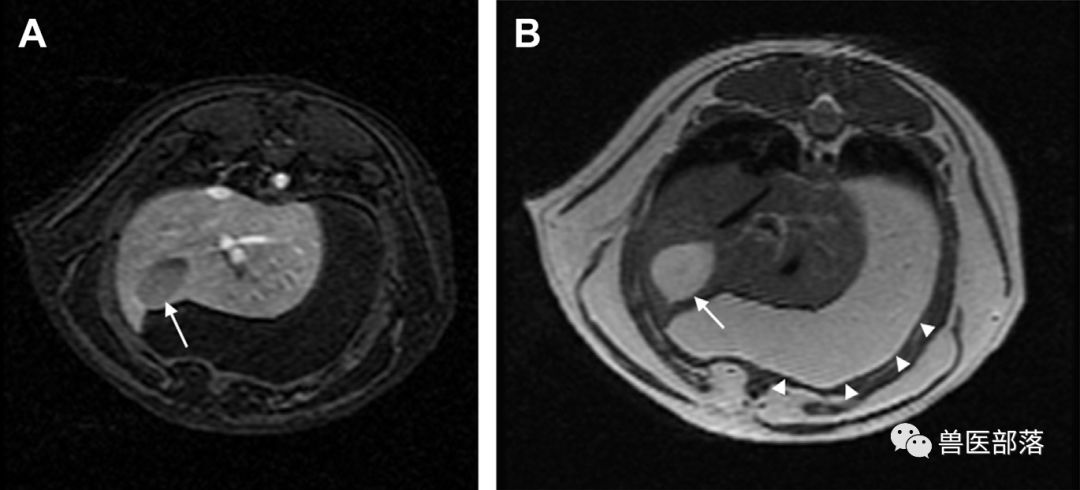

MixiMRI勉強会 脂肪抑制いろいろ 最近やっと勉強する気になったのですが、疑問が次から次へと出てきます。ここでは脂肪抑制についてお聞きしたいと思います。 脂肪抑制にもいろいろありますよね。 T2、PD、T1など。また、SE系、GRE系の違いもありま. ・骨盤部ではmriを,腹部ではctを第一選択にする. ・t1強調画像ではt1が長いほど磁化の回復が遅れるため信号が低く(黒く),t2強調画像ではt2 が長いほど磁化の減衰が遅れるため信号が高く(白く)描出される.t1とt2の組み合わせで組 t1強調画像はctの画像と似ており、脳の解剖学的な構造が見やすいという特徴があります。. 造影剤投与によりT1緩和時間が大きく短縮されますので基本的に脂肪抑制T1強調画像をベースに撮影が行われます。 ③実際の症例を提示します。 1) Stage I 腎細胞癌のdynamic MRI画像です。 左腎臓上極に1cm大の遷延性濃染する腫瘍を認めます。.

放射線技師向け kenminkei11. 2.MRIのパルスシーケンス 表在性軟部腫瘍では病変部位や形態が様々で あり,プロトコールを標準化しづらい.当院で 表在性軟部腫瘍の画像診断 391 図1石灰化上皮腫 (a)(b)(c)後背部正中の皮下腫瘤は,MRIのT1強調像,T2強調像でともに低信号で辺縁に. 肝細胞癌はt2強調画像、拡散強調画像で高信号、t 1 強調画像では低信号を呈している。造影ダイナミック検査早期相ではgd.

MRI ・T2強調像でのjunctional zone. 15分で分かる(?)MRI 古典力学的説明※1 MRI原理へのいざないPart 1 1個のプロトンから15分単位で理解できる(?) 基本的な信号強度 Part 1 プロトン密度、T1、T2と信号強度 ※学部学生は最低でもPart 1を理解すること. 4.mri:撮像法と画像所見 角谷 眞澄 藤永 康成 はじめに 肝疾患の診断にmriが期待されるのは,その優れた 組織コントラスト能によるところが大きい.t1強調像, t2強調像にて肝細胞性結節性病変は様々な信号強度を.